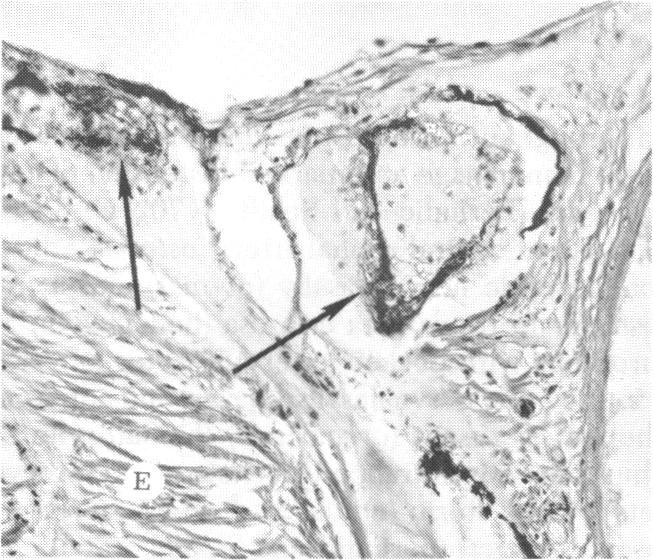

The clinical and histopathologic features of 29 eyes from 29 patients with central retinal vein occlusion (CRVO) are reported. A fresh or a recanalized thrombus was observed in each eye. This study considers the temporal aspects of the cases, and it notes the different morphologic features of the occlusion. These observations explain most of the variability of the changes observed in previous reports. We believe that these different features represent the various stages in the natural evolution of such a thrombus. The interval between CRVO and histopathologic study in our series ranged from six hours to more than 10 years. Local and systemic factors were reviewed and were found to be important in the pathogenesis of thrombus formation. Local diseases with a predisposing effect on CRVO included: glaucoma, papilledema, subdural hemorrhage, optic nerve hemorrhage, and drusen of the optic nerve head. Associated systemic diseases included: hypertension, cardiovascular and cerebrovascular disease, diabetes mellitus, and leukemia with thrombocytopenia. A fresh thrombus in the CRVO was observed in three (10.3%), and a recanalized thrombus in 26 eyes (89.7%). Endothelial-cell proliferation was a conspicuous feature in 14 (48.3%) of the eyes. Chronic inflammation in the area of the thrombus, and/or vein wall or perivenular area was observed in 14 (48.3%) of the eyes. Arterial occlusive disease was observed in seven eyes (24.6%). Cystoid macular edema was found in 26 (89.7%) of the eyes.

报告了29例视网膜中央静脉阻塞(CRVO)患者29只眼的临床和组织病理学特征。每只眼中均观察到新鲜或再通的血栓。本研究考虑了病例的时间因素,并记录了阻塞的不同形态学特征。这些观察结果解释了先前报告中观察到的变化的大部分变异性。我们认为这些不同特征代表了此类血栓自然演变的各个阶段。我们系列中CRVO与组织病理学研究之间的间隔时间从6小时到10多年不等。对局部和全身因素进行了回顾,发现它们在血栓形成的发病机制中很重要。对CRVO有 predisposing 作用的局部疾病包括:青光眼、视乳头水肿、硬膜下出血、视神经出血和视神经乳头玻璃膜疣。相关的全身疾病包括:高血压、心血管和脑血管疾病、糖尿病以及伴有血小板减少的白血病。在CRVO中观察到3只眼(10.3%)有新鲜血栓,26只眼(89.7%)有再通血栓。14只眼(48.3%)中内皮细胞增殖是一个显著特征。14只眼(48.3%)中观察到血栓区域、和/或静脉壁或静脉周围区域有慢性炎症。7只眼(24.6%)中观察到动脉闭塞性疾病。26只眼(89.7%)中发现黄斑囊样水肿。 (注:文中“predisposing”可能是“易患的”意思,但在专业医学语境中,可能有更准确特定含义,这里按常见理解翻译,具体含义需结合医学专业知识进一步确认。)